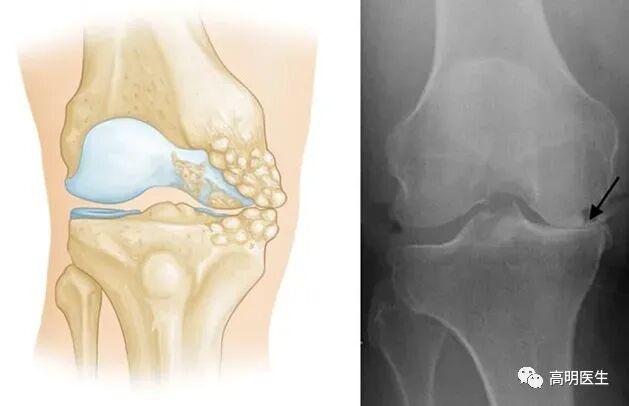

首先明確一點(diǎn):寒冷刺激不是關(guān)節(jié)炎的病因。關(guān)節(jié)炎是一類疾病的統(tǒng)稱,包括骨關(guān)節(jié)炎、類風(fēng)濕性關(guān)節(jié)炎、痛風(fēng)性關(guān)節(jié)炎等,其中最為常見的是骨性關(guān)節(jié)炎。膝關(guān)節(jié)骨性關(guān)節(jié)炎,是一種膝關(guān)節(jié)的退行性疾病,主要臨床表現(xiàn)為膝關(guān)節(jié)疼痛、腫脹及活動(dòng)受限,主要病理表現(xiàn)為膝關(guān)節(jié)軟骨的纖維化、磨損、剝脫等伴發(fā)滑膜充血水腫及骨贅增生等。據(jù)不完全統(tǒng)計(jì),我國(guó) 60 歲以上人群發(fā)病率為 50%,75 歲以上人群高達(dá) 80%,全國(guó)大概有 1.2 億人遭受膝關(guān)節(jié)骨性關(guān)節(jié)炎疼痛的困擾。研究顯示膝關(guān)節(jié)骨性關(guān)節(jié)炎患者中,近 20%會(huì)伴隨焦慮及抑郁癥狀,是導(dǎo)致全世界中老年人生活質(zhì)量降低和經(jīng)濟(jì)負(fù)擔(dān)加重的重要原因。它們的成因各不相同,但都與寒冷無直接因果關(guān)系。

· 骨關(guān)節(jié)炎:最常見的類型,主要由關(guān)節(jié)軟骨的退化引起。年齡增長(zhǎng)、肥胖、過度使用關(guān)節(jié)、遺傳因素等才是主要發(fā)病原因。

關(guān)節(jié)就像汽車輪胎,也有“使用壽命”。隨著年齡增長(zhǎng),關(guān)節(jié)軟骨逐漸磨損,彈性下降,最終出現(xiàn)骨贅(俗稱“骨刺”),這就是骨關(guān)節(jié)炎的過程?。?只不過有些人的關(guān)節(jié)耐磨,有些人的不耐磨罷了。不僅人類,幾乎所有脊椎動(dòng)物都會(huì)得骨關(guān)節(jié)炎,但是對(duì)于一些關(guān)節(jié)負(fù)荷極小的動(dòng)物(如蝙蝠、樹懶等)發(fā)病率極低。這也說明骨關(guān)節(jié)炎是關(guān)節(jié)對(duì)磨損的自然反應(yīng)。